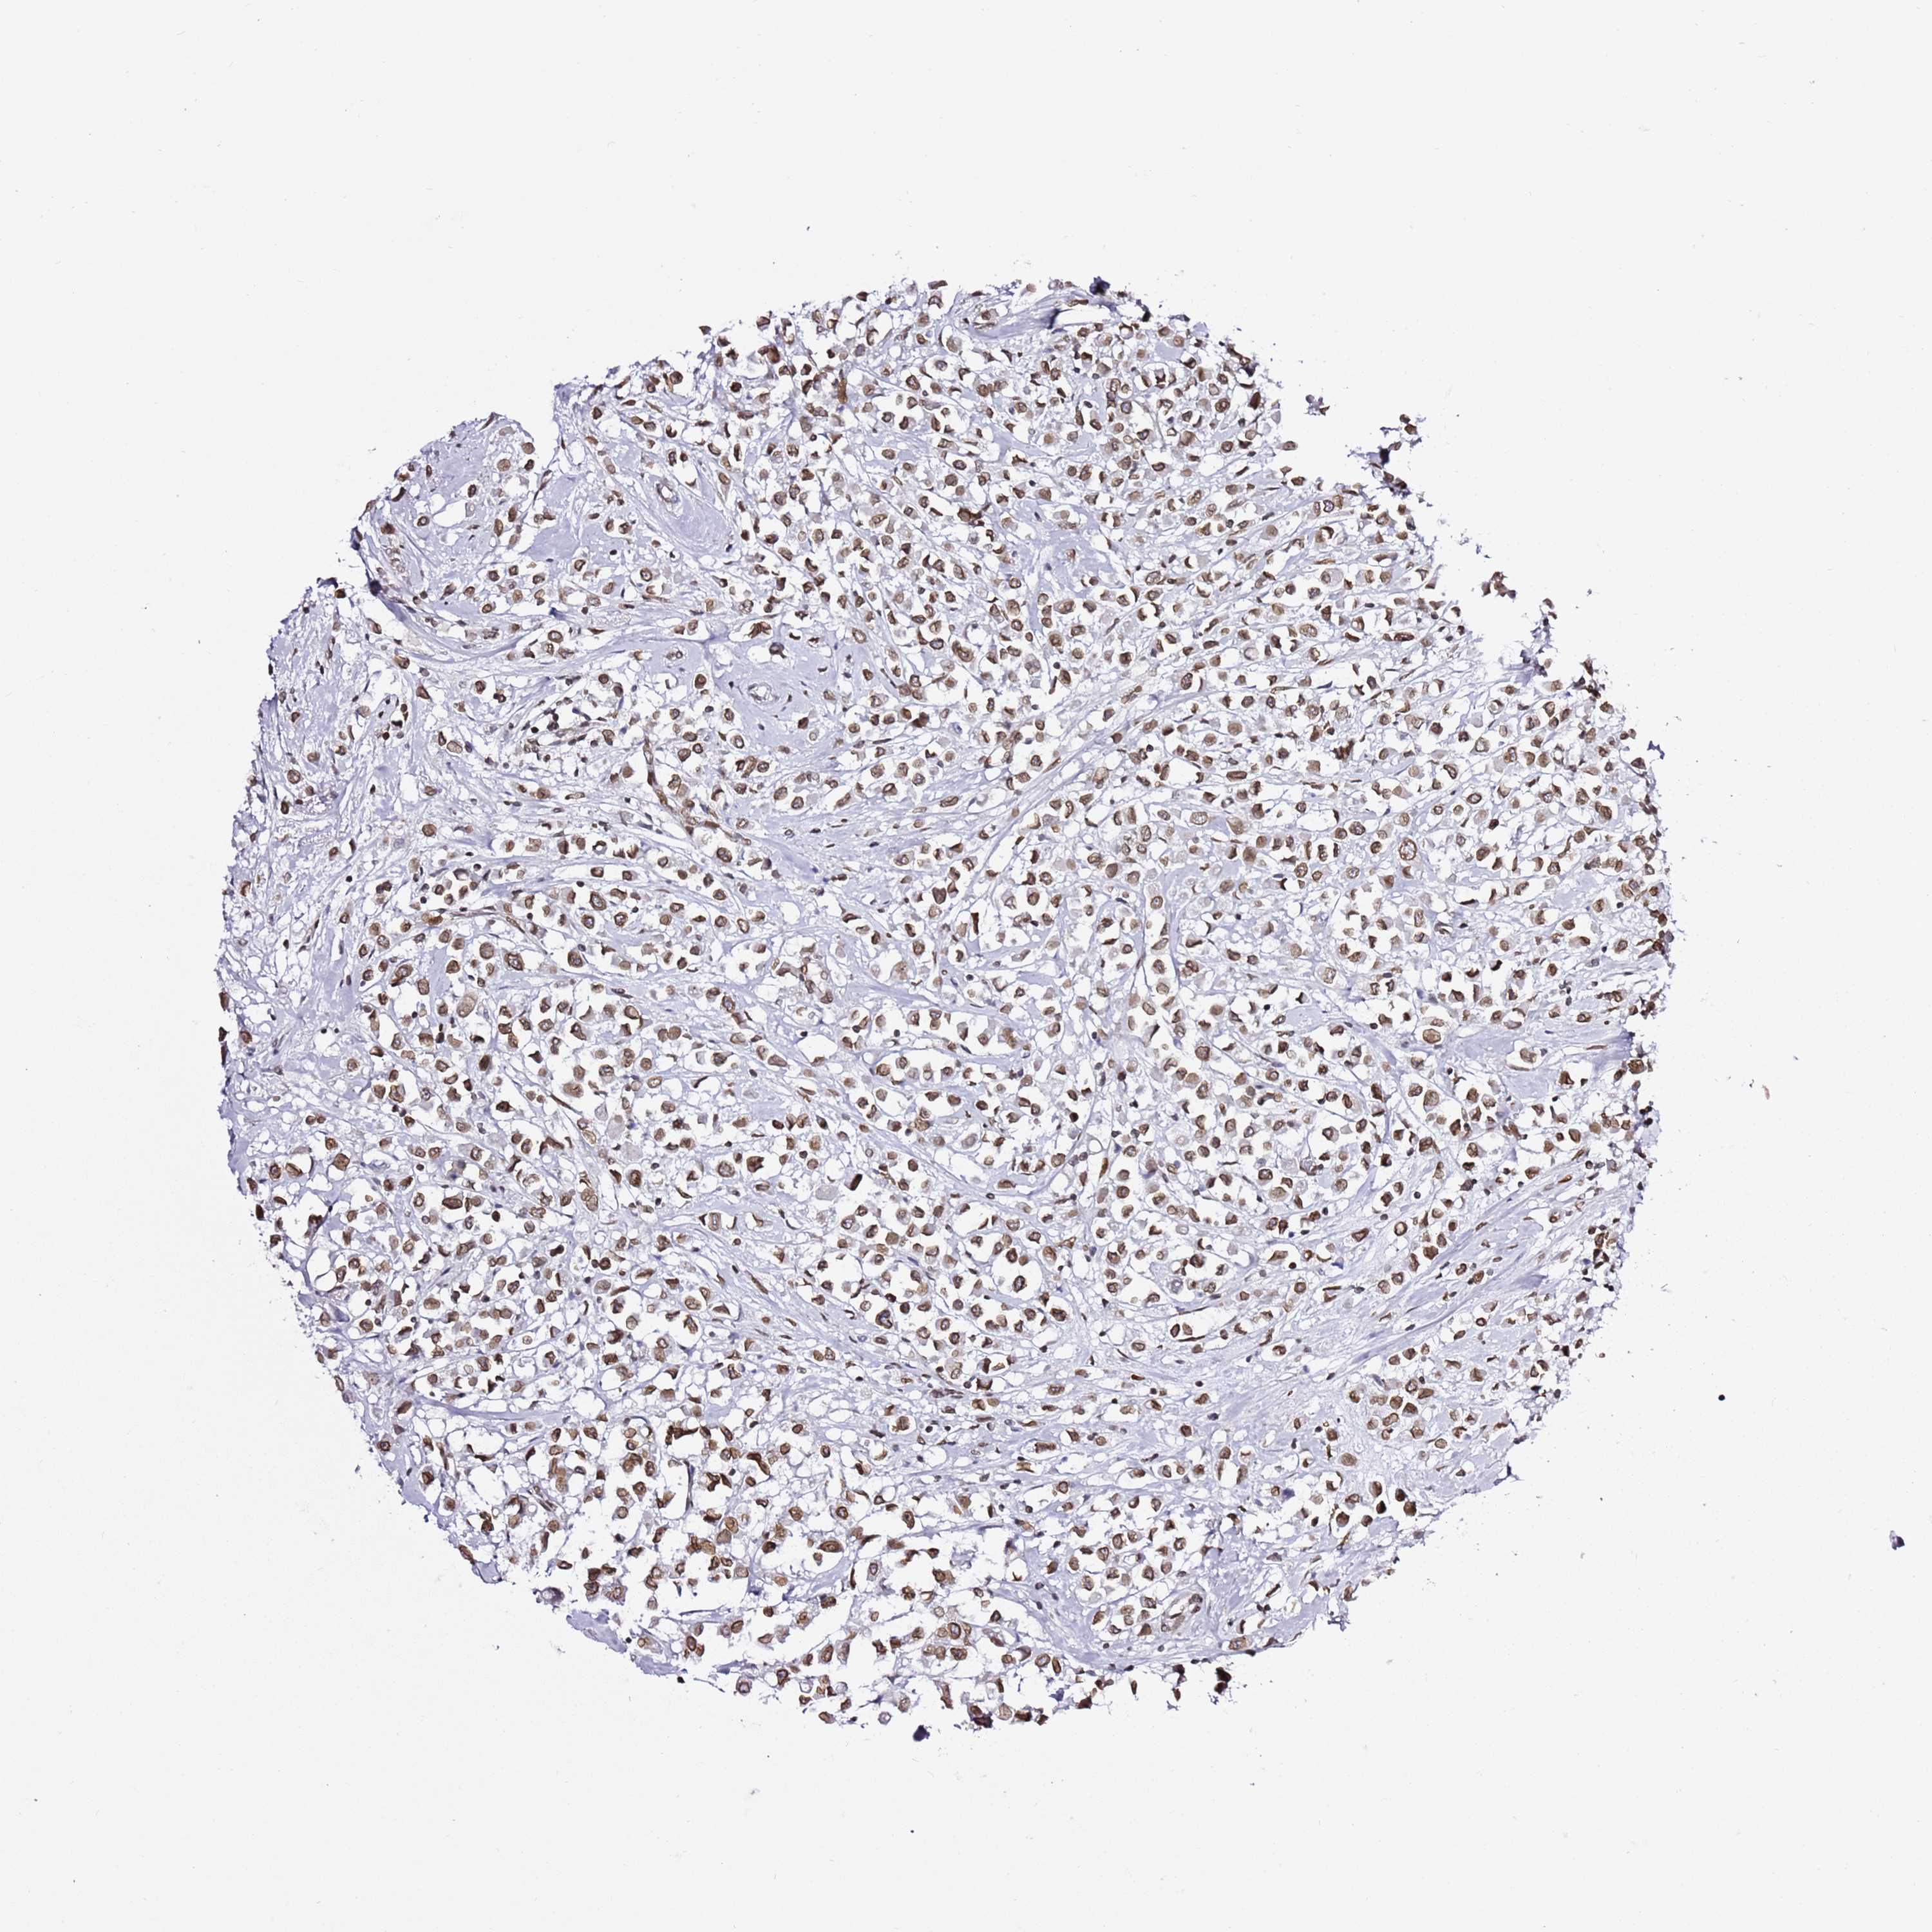

CANCER BREAST CANCER Show tissue menu

BRCA TCGA BRCA VALIDATION PROTEIN EXPRESSION

Breast cancer

Human cancer

Breast invasive carcinoma

POU6F1 is not prognostic in Breast Invasive Carcinoma (TCGA)